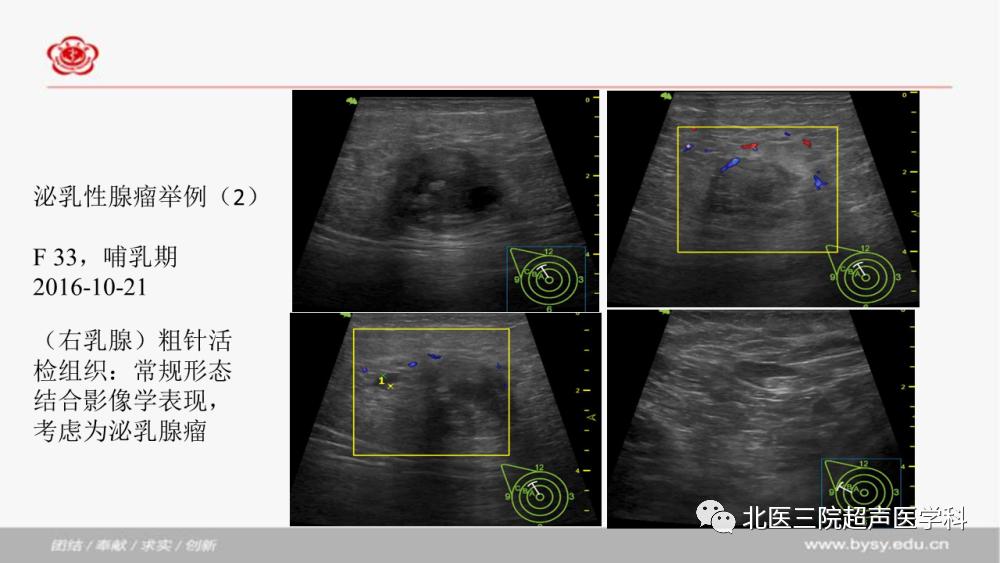

泌乳性腺瘤

发布时间:2020-06-06 点击数: